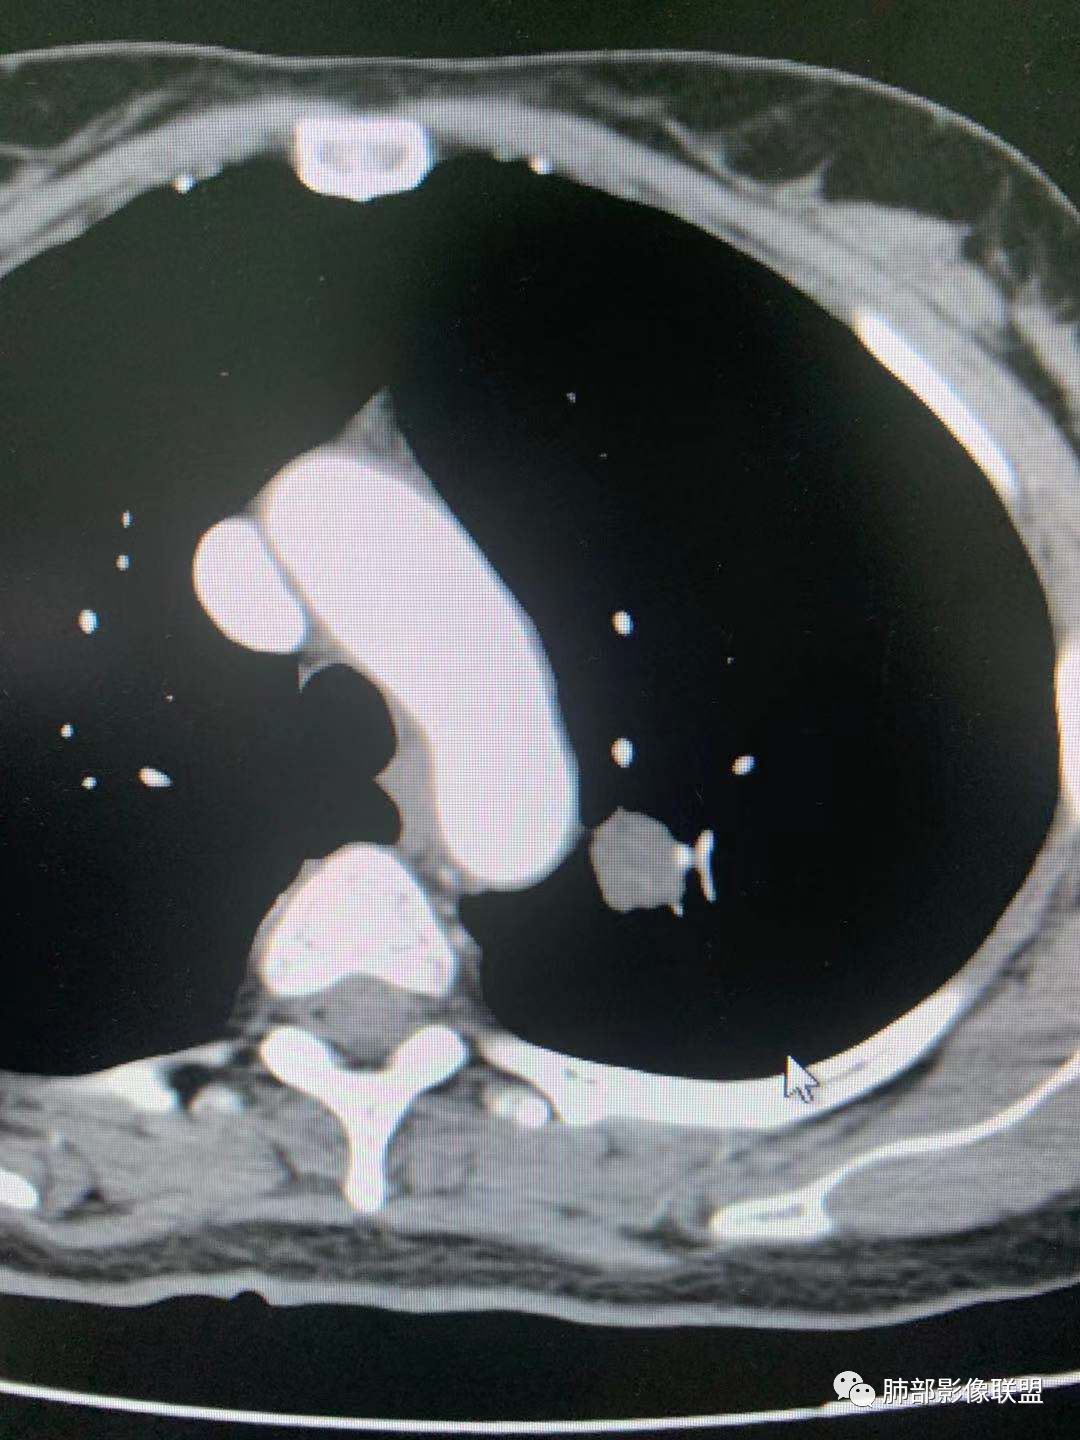

一.尖后段高密度大结节:

1.左肺上叶尖后段较大类圆形实性密度结节影,密度均匀,中等程度强化。

2.实性密度区边缘相当清楚,表面欠光整,偶见毛刺、棘突和旁出血管结构,未见典型的深分叶及邻近胸膜凹陷。

3.可疑支气管进入受阻。可惜缺乏连贯图像或冠矢状位以资判断。

4.病灶与胸膜之间有连线,邻近段支气管及肺血管整体后移,提示病灶还是有一定收缩性。

如上,单就这实性结节,硬化性肺细胞瘤(PSP)和腺癌似乎都能够解释,形态太规整了一些。

5.病灶周围见边界清楚的磨玻璃影,有点醒目,有点意外!

这是无论如何不能忽视的征象!

这点强烈提示,要么整个病灶恶性(腺癌),要么良性病灶旁滋生恶性病灶。

两年前左上肺的病灶什么位置,什么模样,是否相关?我们不得而知。